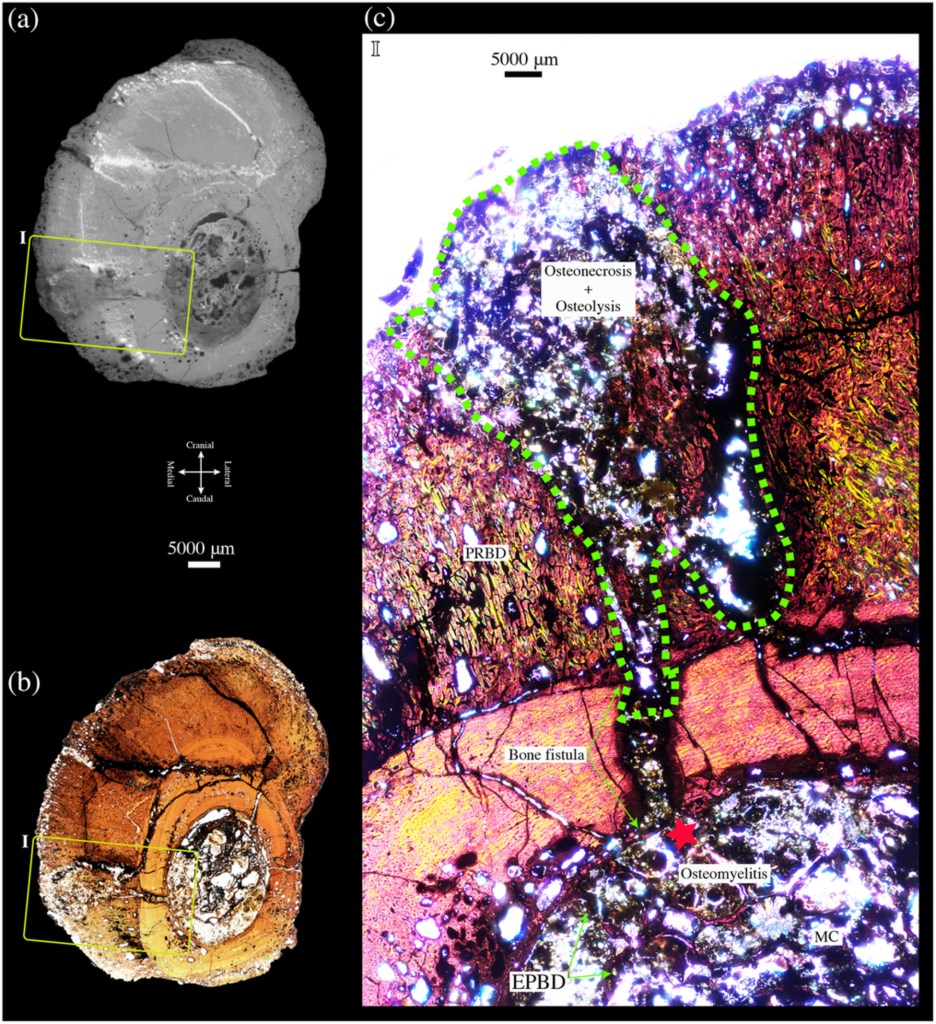

Chinzorig et ses collègues ont effectué un examen anatomique de l’os qui a révélé la présence d’une pathologie sur l’entièreté de la diaphyse de l’os, caractérisée par un dépôt plus important d’os et une surface ondulée et rugueuse. L’imagerie au scanner CT ainsi que les coupes histologiques de l’os ont révélé la présence de plusieurs fractures sur la diaphyse ainsi que de cavités radiotransparentes dans l’os. La croissance de l’os apparaît également perturbée du fait de cette pathologie.

Cette analyse permet d’en déduire que le métatarsien de l’individu MMNS VP-6332 a subi une fracture des suites d’un échec de flexion, et que l’impact a eu lieu initialement sur la partie arrière de la diaphyse de l’os. Des cals de fracture sont observables, structures crées par le corps pour unifier les fragments d’os dus à la fracture, signes d’une guérison avancée. Toutefois cette guérison a subi un retard, probablement causé par une ostéomyélite chronique (infection osseuse) observée sur l’os par Chinzorig et ses collègues. Des agents pathogènes ont également pénétré la fracture, créant ce que l’on appelle une fistule osseuse. Toutes ces complications ont entraîné un retard de guérison et une ostéonécrose partielle de l’os. Il est toutefois impossible de savoir si ces pathologies ont entraîné la mort de l’individu.